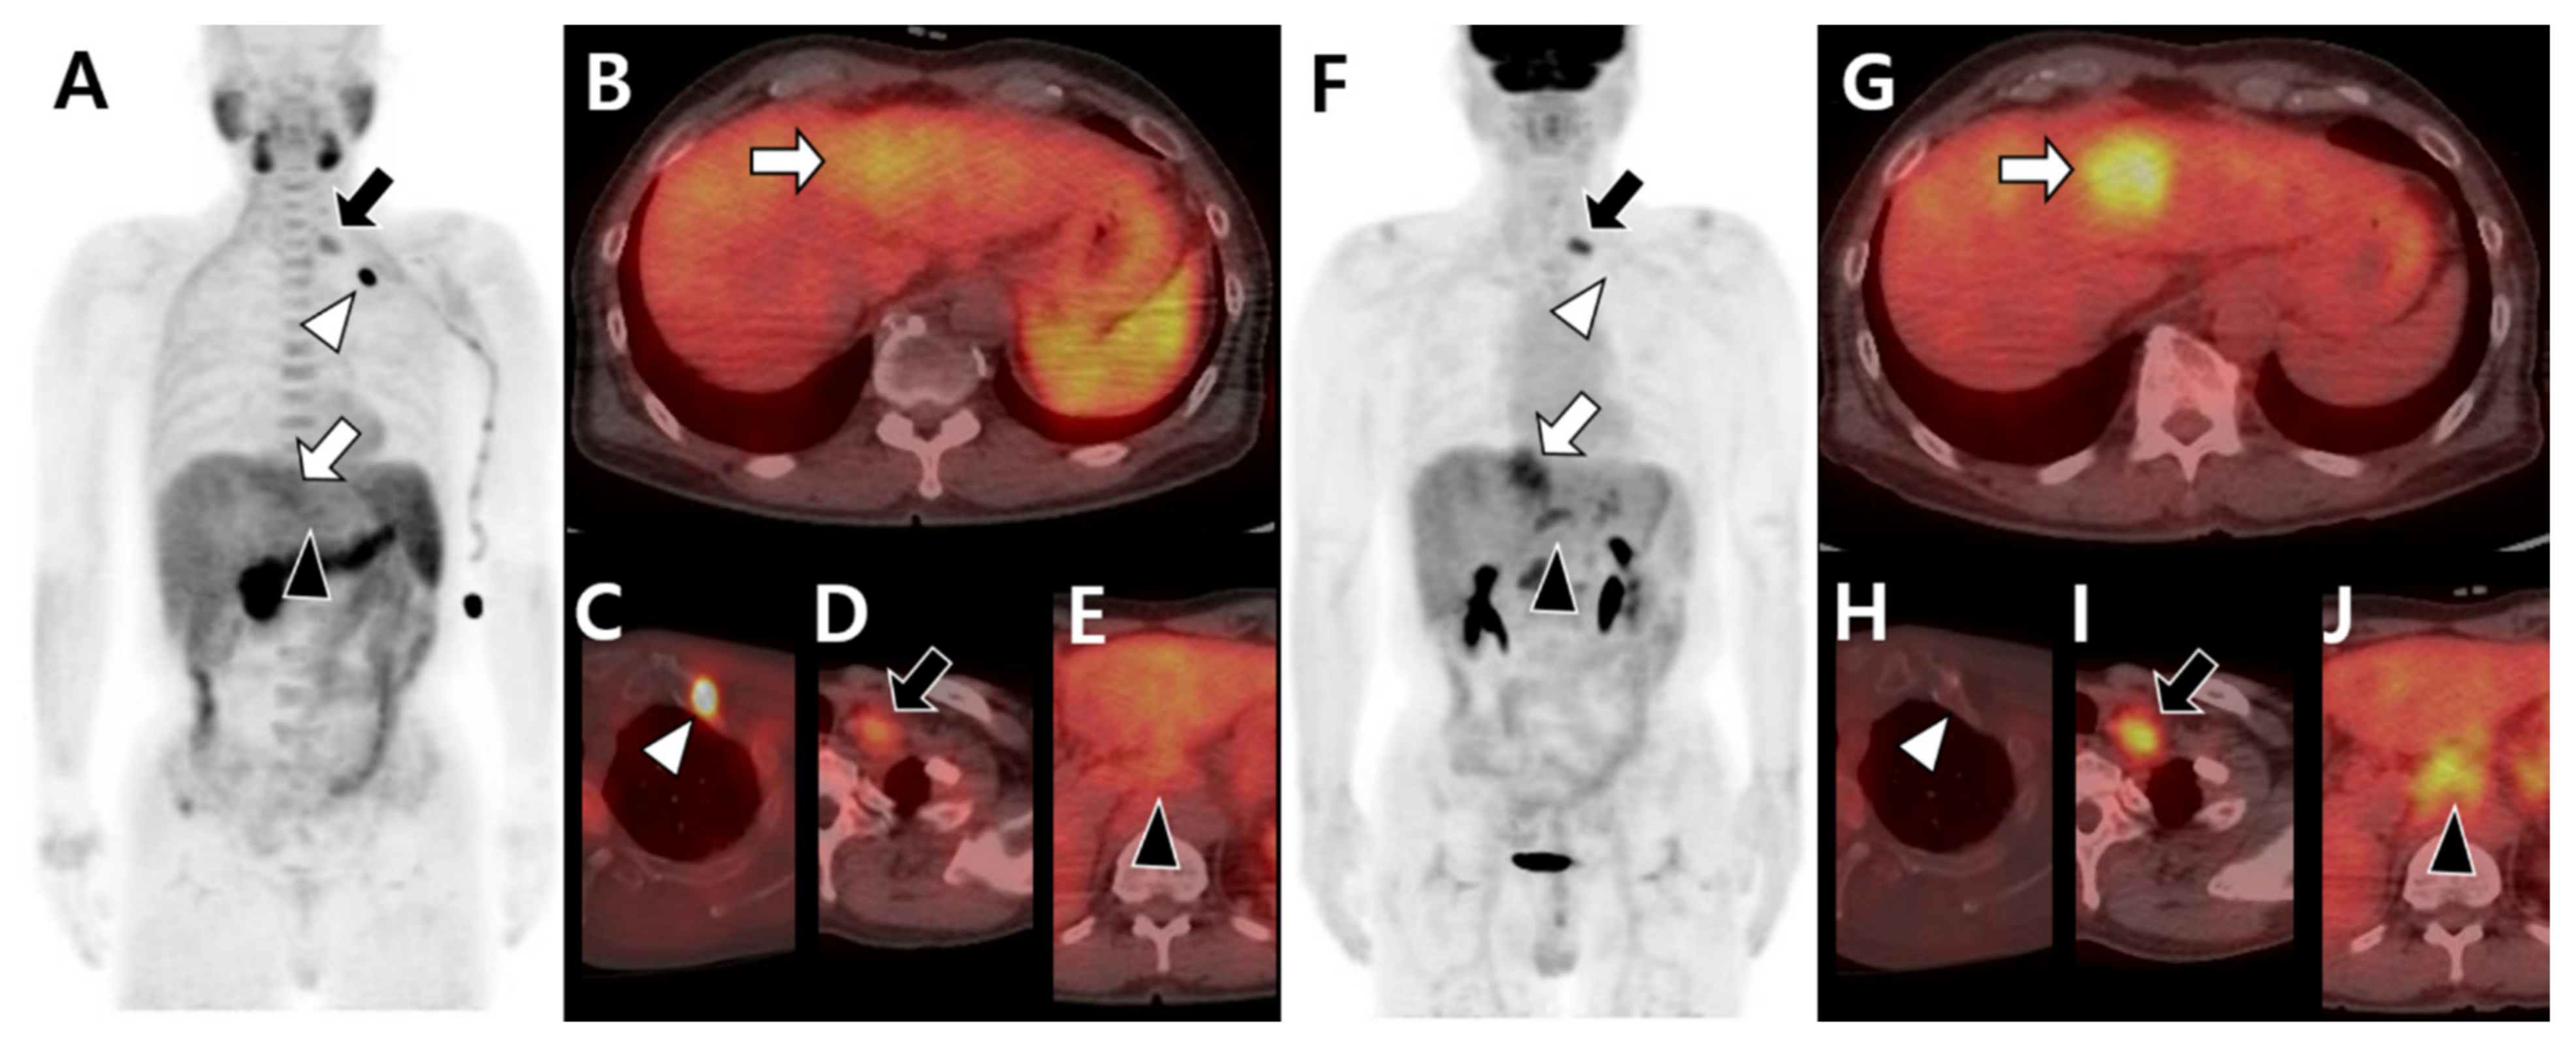

Figure 4.

Different tracer avidity according to the metastatic organ in the same patient with hepatocellular carcinoma before therapy. 11C-acetate positron emission tomography (PET)/computed tomography (CT) (A–E) shows mild uptake in the primary hepatic tumor (white arrow in A,B). The metastatic bone lesion in the left first rib shows intense acetate uptake (white arrowhead in A,C) but less acetate uptake in metastatic lymph nodes of the left supraclavicular (black arrow in A,D) and common hepatic (black arrowhead in A,E) areas. 18F-fluorodeoxyglucose (18F-FDG) PET/CT (F–J) shows intense uptake in primary hepatic tumors (white arrow in F,G). There is no significant FDG uptake in the left first rib (white arrowhead in F,H) but intense uptake in the left supraclavicular (black arrow in F,I) and common hepatic (black arrowhead in F,J) lymph nodes.

Figure 5.

Different tracer avidities according to involved sites of bone metastases in the same patient with hepatocellular carcinoma before therapy. 11C-acetate positron emission tomography (PET)/computed tomography (CT) (A–D) shows intense acetate uptake in metastatic lesions of the left third rib (white arrow in A,B) and sacrum (white arrowhead in A,D) but mild acetate uptake in the T12 vertebra (black arrow in A,C) and left iliac bone (black arrowhead in A,D). 18F-fluorodeoxyglucose (18F-FDG) PET/CT (E–H) shows mild FDG uptake in the left third rib (white arrow in E,F) and sacrum (white arrowhead in E,H) but intense FDG uptake in the T12 vertebra (black arrow in E,G) and left iliac bone (black arrowhead in E,H).